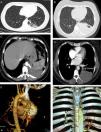

We report a case of a 36 year-old woman, never smoker, observed in the outpatient clinic for recurrent pneumonias. Over the past 5 years, she reported several pneumonias, all slowly resolving and in need of multiple courses of antibiotics. Between infections she complained of dry cough and left pleuritic chest pain. She worked as a care assistant in a continuing care unit and apart from the recurrent infections had no other significant medical history. Physical examination was unremarkable and laboratory findings and bronchoscopy were normal. Chest X-ray showed a reticular opacity in the left lower field and a computed tomography (CT), performed two months earlier, showed a heterogeneous consolidation on the left lower field with millimetric air spaces compatible with cysts (Fig. 1A). Chest CT was repeated, revealing a 10 cm heterogeneous consolidation on the left inferior lobe, with arterial supply arising from the thoracic descending aorta and venous drainage to the pulmonary veins (Fig. 1B–F). The second CT was performed during another infectious episode and radiologic findings suggested IL-PS with superimposed infection. The infection was resolved and the patient was submitted to left inferior lobectomy with an uneventful post-operative recovery. Surgical procedure confirmed the anomalous vascularization and histological findings were compatible with CCAM type 2. A diagnosis of CCAM type 2 associated with IL-PS was established based on imaging and histological findings. The patient remained asymptomatic 1 year after surgery.

Fig. 1. (A) The first chest CT performed, showing a heterogeneous posteromedial consolidation in the left lower lobe comprising multiple cysts. (B) The second chest CT showing posteromedial hepatization of the left lower field, compatible with superimposed infection. (C) CT angiography showing the anomalous artery arising from the thoracic aorta. (D) CT angiography images showing the venous drainage (arrow) to the pulmonary veins. (E–F) 3D CT reconstructions showing the anomalous artery.